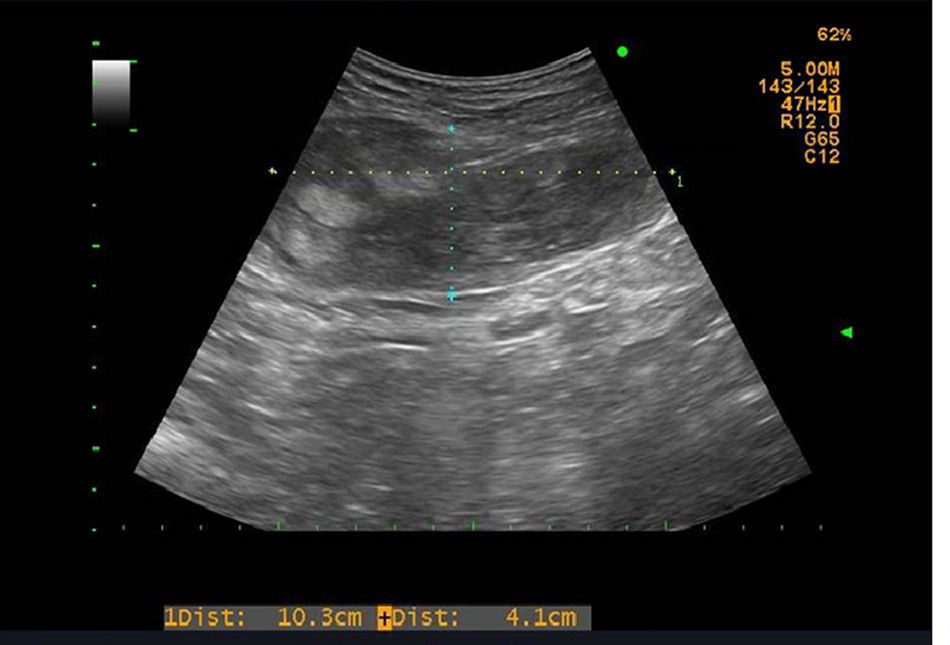

Se solicitaron una analítica y una ecografía abdominal urgentes. En la ecografía (fig. 1) se observaba un notable engrosamiento del músculo recto anterior del abdomen, visualizando un área irregular de ecogenicidad heterogénea de unos 10cm de eje craneocaudal y 4cm de eje anteroposterior, compatible con un hematoma intramuscular.

El diagnóstico se confirma con la realización de una ecografía o una TC abdominal con una elevada sensibilidad6,10, aunque el punto más importante es pensar en esta dolencia y realizar una correcta anamnesis y exploración del paciente5. En la ecografía se observa una lesión ocupante de partes blandas, heterogénea, con áreas hipoecoicas que alternan con áreas hiperecoicas, y en la TC, una masa de partes blandas contenida dentro del músculo, homogénea o heterogénea; en caso de que exista hemorragia activa podemos detectar el punto sangrante con la administración de contraste intravenoso.